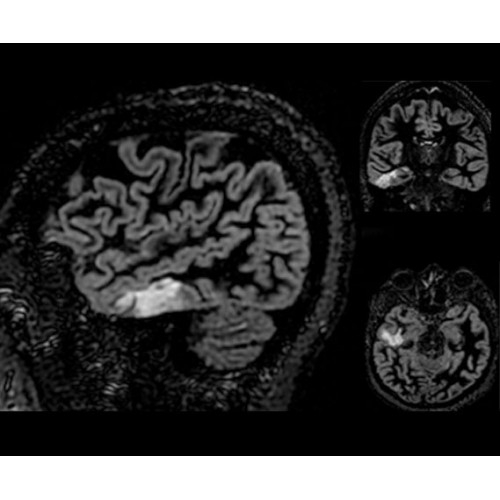

SIGNA PET/MR 3.0T — это гибридная система, в которой совмещаются две принципиально разные технологии — магнитно-резонансную томографию (МРТ) и позитронно-эмиссионную томографию (ПЭТ). Система отличающийся высокой чувствительностью и эффективностью и предназначена для диагностики в области онкологии, неврологии, кардио-васкулярных исследований, исследований воспалительных процессов.

Компания GE Healthcare представляет революционную, полностью интегрированную систему SIGNA PET/MR1, в которой сочетаются времяпролетная технология (TOF) и возможности напряженности магнитного поля 3.0 Тл. Мы поможем вам поднять исследования на более высокий уровень. SIGNA PET/MR позволяет достичь впечатляющей точности и скорости исследований, а благодаря новейшей технологии реконструкции Q.Clear2 качество изображений улучшается в два раза. Кроме того, в систему включен полный набор клинических приложений и гибких катушек для проведения любых видов исследования, открывая для вас возможности визуализации, о которых вы даже не догадывались.

В систему SIGNA PET/MR встроены запатентованные детекторы кремниевого фотоумножителя (SiPM) и сверхчувствительные кристаллические сцинтилляторы на основе лютеция толщиной 25 мм. Благодаря этому обеспечивается исключительная чувствительность и возможность использования времяпролетной диагностики (TOF).

Кроме того, в результате использования технологии TOF и инновационной технологии реконструкции Q.Clear вы сможете добиться прекрасного соотношения сигнал/шум. А благодаря технологии нулевого времени эхо (ZTE) визуализировать костную структуру без ионизирующего излучения. Все эти разработки для улучшения качества сканирования и точности анализа помогут вам использовать весь потенциал ПЭТ/МРТ.

• Специальный пакет приложений для измерения и сравнения объемных изображений ЦНС с нормами поможет вам в диагностике нейродегенеративных заболеваний, а дополнительные инструменты визуализации — в постановке точного диагноза с помощью бета-амилоидов и радиоизотопных маркеров ФДГ.